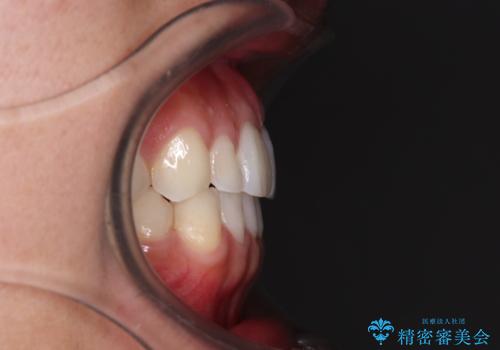

前歯のデコボコとクロスバイト インビザライン矯正治療

- 前歯のデコボコとクロスバイトを治したいとのことで来院された患者様です。

上下顎ともに歯列全体の側方拡大を行い、下顎前歯はIPR(歯と歯の間を削る)によってデコボコとクロスバイトが解消するように設計し、インビザラインにより治療を行うこととしました。

2年弱で終了する予定でしたが、途中来院されなかった時期があり、その後舌側転位している前歯を動かせるところまで動かしたいとのことで4年ほど治療を継続されました。